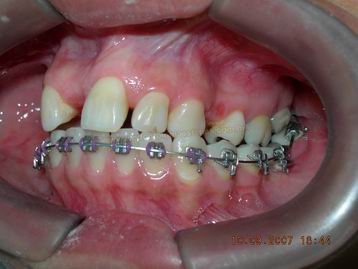

VISTA LATERAL DURANTE FASE DE ALINHAMENTO E NIVELAMENTO INFERIOR |

VISTA LATERAL DURANTE FASE DE ALINHAMENTO E NIVELAMENTO BIMAXILAR |